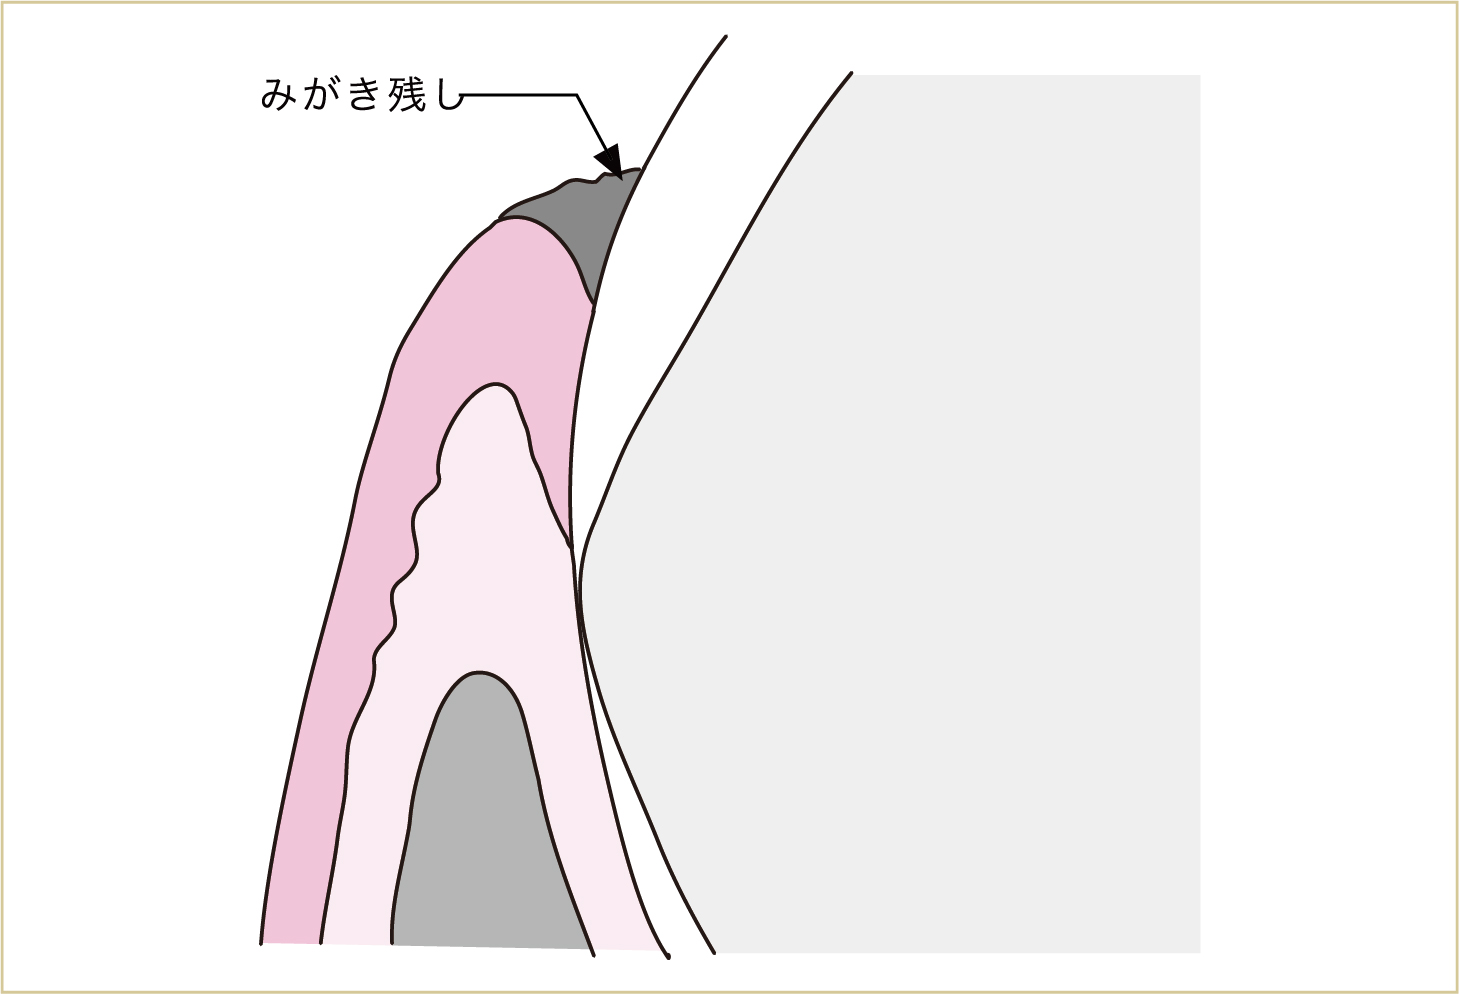

まず、ものを食べたり飲んだりすると、歯と歯肉の間の溝(歯肉溝、歯周ポケットと呼ばれる)などに汚れがたまります。

また、歯と歯肉の間の溝は、ブラッシングする際に、みがき残しができやすい場所でもあります。

歯と歯肉の溝にみがき残しができる。